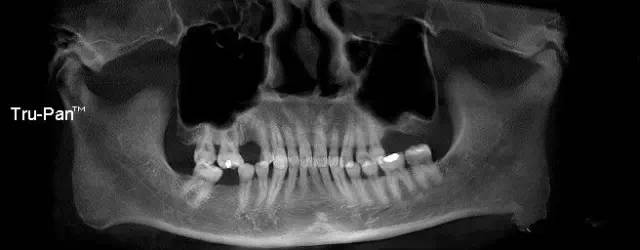

第四圖:上頜竇發(fā)育不足,上頜竇底骨高度充裕,通常頰側(cè)骨壁超級厚,看下圖2.臨床上種植常不需要提升措施。(如需提升,切記頰側(cè)骨厚度過大,開窗的困難性劇增)